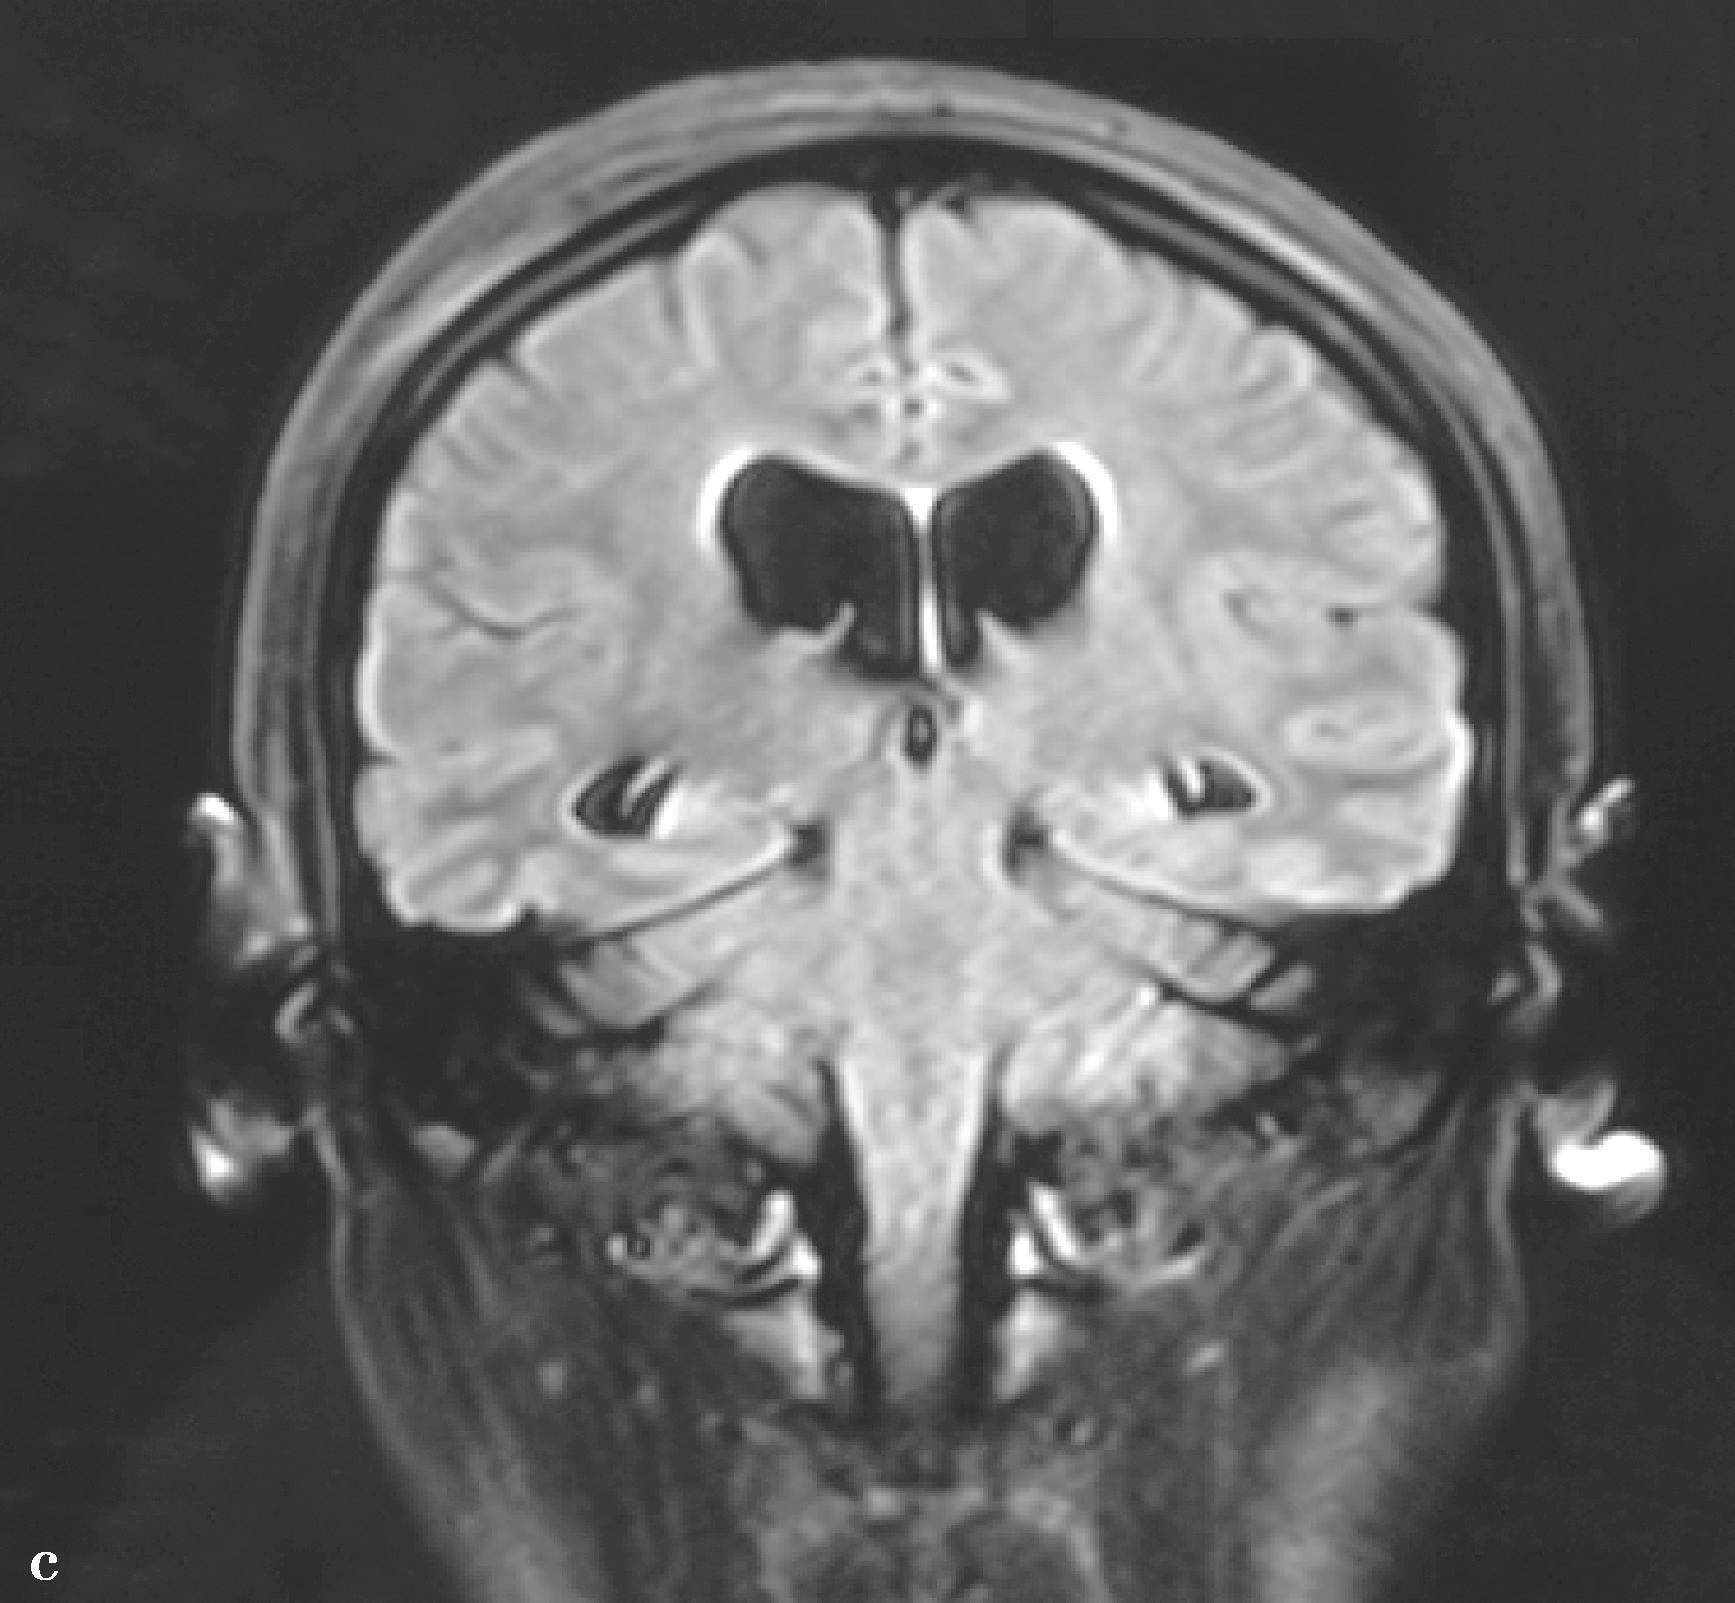

图3-1-2-11 脑积水合并Chiari畸形

a.术前MRI矢状位片示脑积水,小脑扁桃体下疝;b.第三脑室底造瘘术后1周,MRI矢状位片示小脑扁桃体下疝减轻